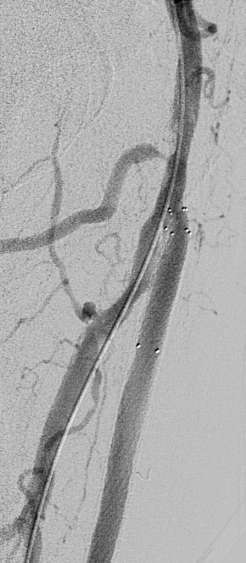

溃疡继续恶化5天后,血管造影显示足背动脉闭塞。足底动脉通过侧支循环建立。

通过以前的内膜下间隙,将足背动脉再通,并2.5mm球囊扩张

胫前动脉术前闭塞

开放